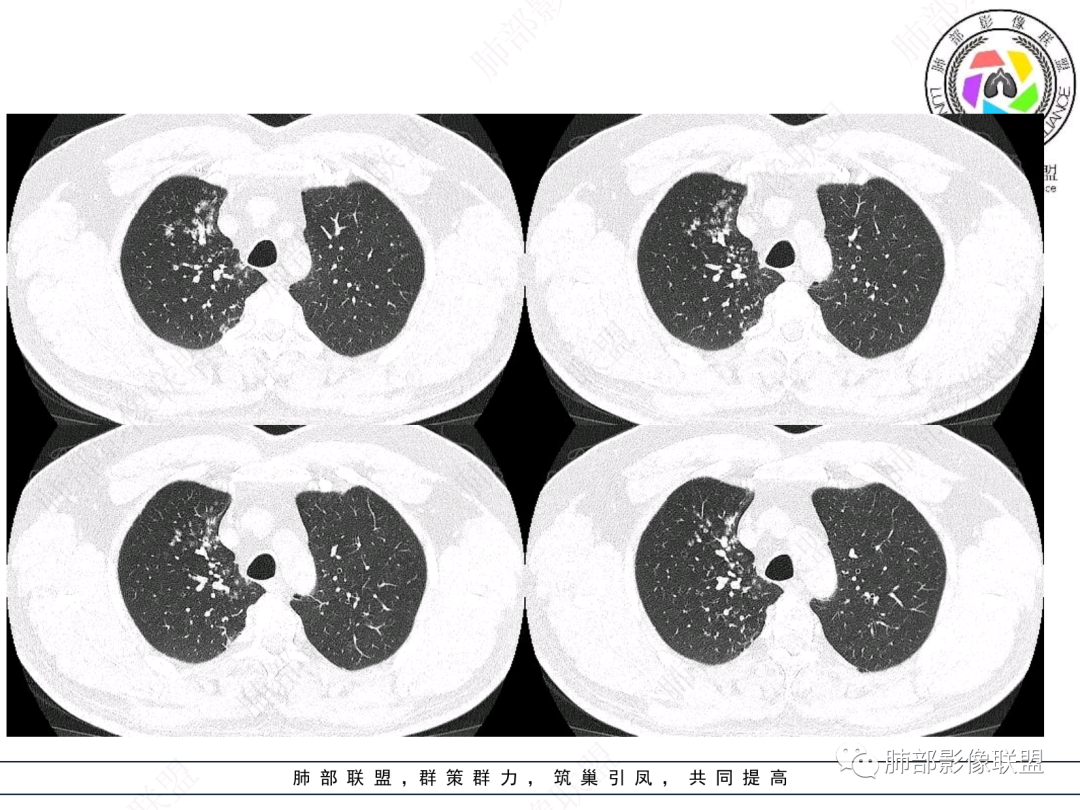

右肺上叶支气管截断,内见软组织密度结节,支气管管壁破坏,病变侵及管外,增强强化明显。右肺上叶沿气管血管束多发斑片影,考虑恶性性病变并阻塞性炎症,鳞癌,神经内分泌肿瘤。

老年男性,咳嗽咳痰,右肺门增大,右主支气管开口见高密度影,密度不均匀,轻度强化,右肺上叶见多发腺泡结节,支气管管壁增厚,近端粘液栓,支气管镜检查见新生物,考虑鳞癌,鉴别结核。

右主支气管及肺门不规则软组织结节,点状钙化,不均匀强化,气管壁破坏,上叶支气管阻塞,分支粘液栓,血管束增粗,沿支气管分布多发结节,考虑鳞癌合并阻塞性炎症,鉴别结核。

右气管腔内结节,右肺门肿物,有钙化,右侧肺内多发气腔结节,散在,左肺部分支气管壁增厚,首先分析气管内结节,多考虑1鳞癌,形态规则,边缘光滑,宽基底,不太支持,远端阻塞性炎症不典型,2类癌,冰山一角和冰山分离了,不太支持3结核,多为支气管壁广泛增厚钙化,形成结节少,但是肺门肿块有钙化,可作为结核支持点,4黏痰,不像。其他不太懂了,肺内多发磨玻璃结节,并可见支气管手指状扩张,综合分析影像,考虑感染性病变,结核?有没有这样子的气管曲霉呢?向老师们学习。

老年男性,右肺门主支气管腔内软组织肿块影,密度不均,有钙化,右上叶支气管腔部分阻塞,强化较明显,右肺上叶远端散在斑片状高密度影,相应支气管壁厚,树丫状腺泡结节,常规首先考虑结核,鉴别类癌。

男,52。间断咳嗽、咳痰2周,加重3天。胸部CT:右主、右上叶支气管多发软组织影,跳跃不连续,内可见小环状高密度,点状钙化,管壁破坏,上叶支气管堵塞,远端分支粘液栓,可见小支气管管壁增厚、管腔狭窄,沿支气管分布多发结节,无大片炎症不张。考虑:TB?NTM?鉴别Ca并阻塞性炎症。

患者中老年男性,咳嗽咳痰2周,无发热、咯血,伴胸闷、乏力及盗汗等,右上叶沿支气管血管束分布结节样变,管壁增厚;右肺门肿块,形态不规则、密度欠均匀,似有钙化,轻强化,主气道下端及右主支气管开口处见新生物,强化不支持类癌,镜下病变形态不大支持腺样囊性癌,考虑鳞癌可能性大,右肺上叶病变结核可能。

右肺上叶支气管开口见阻塞物影及强化,息肉样向腔内外浸润性生长,并有颗粒钙化,右肺上叶段支气管主干增粗及密度增高,见指套征,支气管血管旁见多发小斑点,小斑片影阻塞性炎性病灶〈小花小草表现〉,支气管镜示新生物血供丰富(结核完全排除),方向恶性,符合鳞癌特点,与小细胞Ca鉴定,临床专科支气管镜取材活检明确诊断。

腔内肿物,强化不均匀,强化程度为轻中度强化(CT值增加25HU),且强化特点为快进快出,右肺上叶支气管责任区域的阻塞性炎症加痰栓(气管镜也证实右上叶支气管内痰多)。这些均明确指向鳞癌。

一点不异常啊,分布在阻塞责任气管区域的支气管增粗伴腺泡结节(细支气管腔内及肺泡内阻塞性炎症伴痰栓),只不过还没有大片实变而已。@韩平     临沂市人民医院呼吸科

这个病例比较好,我们的观察点在哪?这是右上叶支气管病变,需要了解:腔内、壁、腔外、远端,腔内有软组织密度影,近端膨隆。

影像上分析的观察点:腔内、壁、腔外、远端,然后就是远端肺组织、淋巴结、肺血管、胸膜、其他肺部,这个人就是阻塞性炎症为主。